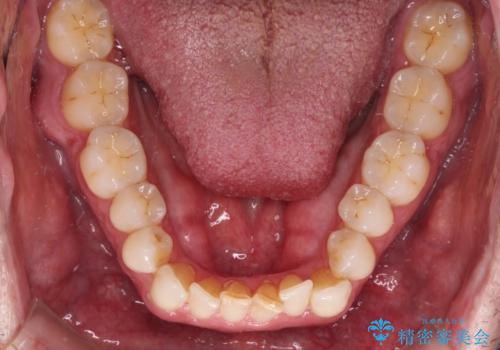

- 前歯でものを噛みきりたいとのことで来院された患者様です。

以前矯正治療を経験されたそうですが、舌の突出癖により上下前歯に隙間ができている様子でした。

舌の突出癖が改善されない限り、非接触改善は見込めないため、トレーニングを徹底するように指示しました。